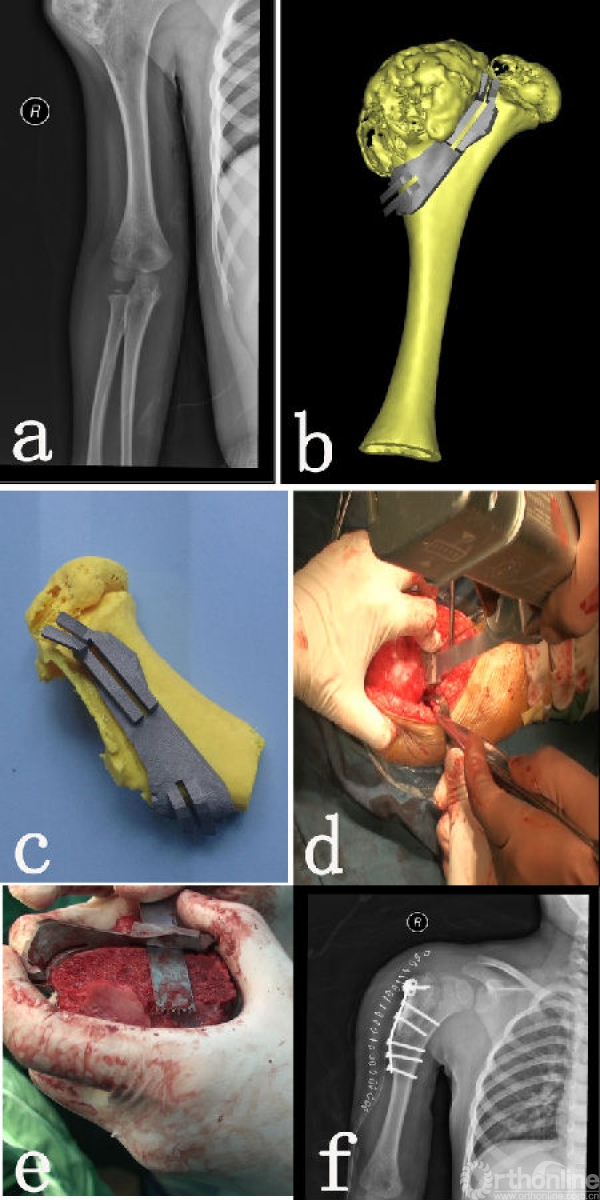

图2:患儿6岁,男性,右肱骨近端骨软骨瘤。

图说 2a手术前X线片,可见右肱骨外侧骨软骨瘤;

2b手术设计切除肿瘤并最大程度保留骨骺,并设计金属导板;

2c3D打印加工好的金属导板及ABS试模;2d术中导板引导摆锯截骨;

2e肿瘤切除后验证,可见按手术设计完整切除;

2f术后X线片可见肿瘤切除彻底,重建稳定。